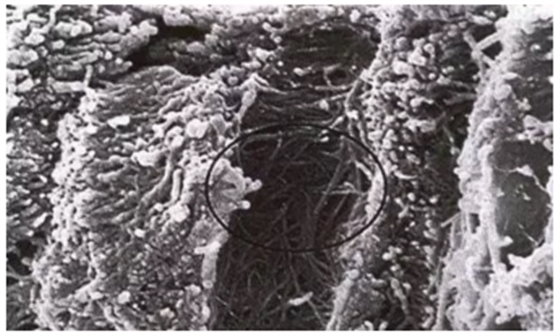

水分有助于保持牙本質(zhì)膠原纖維網(wǎng)的膨松狀態(tài),使其中的微孔開放,可有利于樹脂的滲透。掃描電鏡下顯示,過度干燥的牙本質(zhì)表面會出現(xiàn)膠原纖維網(wǎng)的皺縮和坍塌,不利于粘結(jié)性樹脂單體的滲透,因而不能實現(xiàn)粘結(jié)的微機械固位。因此,存留的水量很關(guān)鍵,過度濕潤或干燥均會引起粘結(jié)強度下降。

詳細了解自酸蝕、全酸蝕

膨松狀態(tài)

皺縮和坍塌狀態(tài)